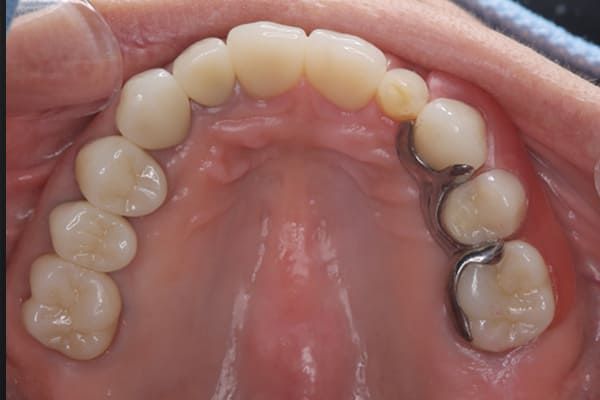

下顎治療後

治療前の入れ歯の奥歯は、治療後の義歯と比較しても分かるように、歯が削れ平らになった状態です。

これにより奥歯のかみ合わせは低くなり、前歯のみが強くあたり、かみ合わせにより上の前歯大きな負担がかかっていたことにより、上の前歯が折れたことが考えられます。

精密義歯は、歯をぬいたあと歯肉が治ってから、精密な入れ歯を作製しました。治療中も、仮の入れ歯があるため、普段の生活に支障がなく、また仮の入れ歯を実際使ってのご意見、ご希望(バネが気になる)をお聞きした上で、精密な義歯に、ご希望を反映し作製しました。